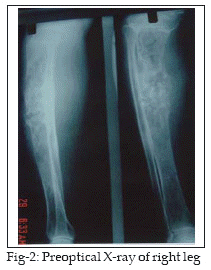

A 71 year old female from a village near by Ahwaz city southwestern part of Iran was admitted to Imam Khomeini hospital in 2003 with swelling, edema and sinus secretion in middle and front of right leg. The patient had an operation 7 years ago because of pain and swelling at the upper and middle third of right tibia. After the operation she had permanent sinus secretion in the middle of her leg, but she has not any information from previous operation. She was under antibiotic therapy. Recent admission was because of warmness, edema, swelling, and sinus secretion in middle and upper of right leg (Fig-1). Radiologic examination revealed osteolytic honeycomb appearance lesions with no reactive bone and incomplete fractures were also noted (Fig-2). Abdominal sonography was normal. Laboratory findings in the first day of admission are shown in Table-1.